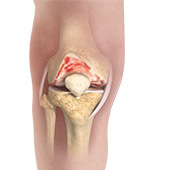

The joint surface is covered by a smooth articular surface that allows pain-free movement in the joint. Arthritis is a general term covering numerous conditions where the joint surface or cartilage wears out. This surface can wear out for several reasons; often the definite cause is not known. Arthritis often affects the knee joint. When the articular cartilage wears out, the bone ends rub on one another and cause pain. The most common type of arthritis is osteoarthritis. It occurs with aging and use.

Osteoarthritis also called degenerative joint disease, is the most common form of arthritis. It occurs most often in older people. This disease affects the tissue covering the ends of bones in a joint (cartilage).In a person with osteoarthritis, the cartilage becomes damaged and worn out causing pain, swelling, stiffness and restricted movement in the affected joint. This condition most commonly affects the joints in the hips, knees, hands, and spine. Rarely, the disease may affect the shoulders, wrists, and feet.